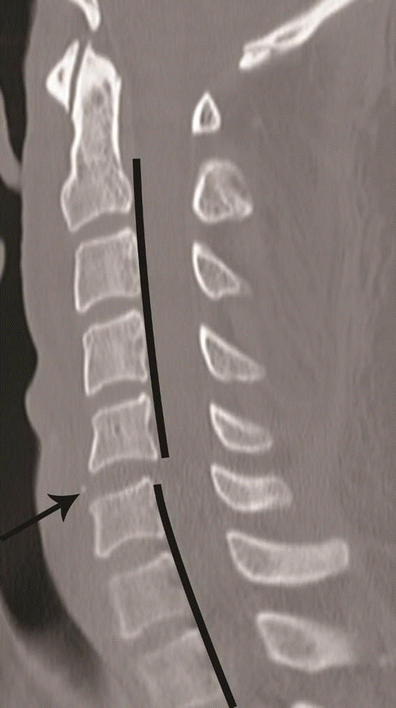

Hyperflexion distraction injury. Mid-sagittal CT image of the cervical spine shows focal kyphosis with posterior disc space widening at C4–C5 (short arrow). Mild anterolisthesis of C4 over C5 is seen suggested by the disrupted posterior vertebral line (black lines). The spinolaminar line is also disrupted with at C4–C5 with anterior displacement of C4 spinolaminar junction (white lines). Widening of the C4–C5 interlaminar/interspinous space (long arrow) is noted. Combination of this pattern of injury is highly suggestive of hyperflexion distraction injury and the facet joint should be carefully evaluated on lateral parasagittal images for possible distraction, subluxation and dislocation (shown in Fig. 13)

Facet joint injury spectrum resulting from hyperflexion distraction. Parasagittal CT images. a The C4–C5 facet joint shows diffuse widening—diastasis (black arrow), and the C5–C6 facet joint shows focal anterior widening (white arrow), suggestive of distraction injury and partial disruption of facet joint capsule. Articular surfaces are congruent and no uncovering of the inferior articular process noted at any of the injured levels. b C5–C6 facet joint subluxation (black arrow), suggested by non-congruent articular surfaces of the facet joint with anterosuperior displacement of the inferior articular process of C5, resulting in partial uncovering of the superior articular surface of C6. However, some apposition of articular surface is still intact. C6–C7 facet joint dislocation (white arrow) suggested by anterior and superior translation of inferior articular process of C6 resting on the top of the C7 articular process, resulting in complete loss of articular apposition and uncovering of C7 articular facet. A facet joint injury as seen at C6–C7 is also named as a “perched facet”. c C6–C7 facet joint dislocation with further anterior translation of the inferior articular process (white arrow), now resting anterior to the C7 articular pillar. This injury is also called a “locked” or “jumped facet”